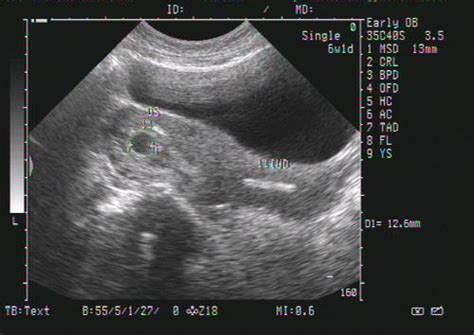

怀孕8个月b超图分析 8个月彩超图